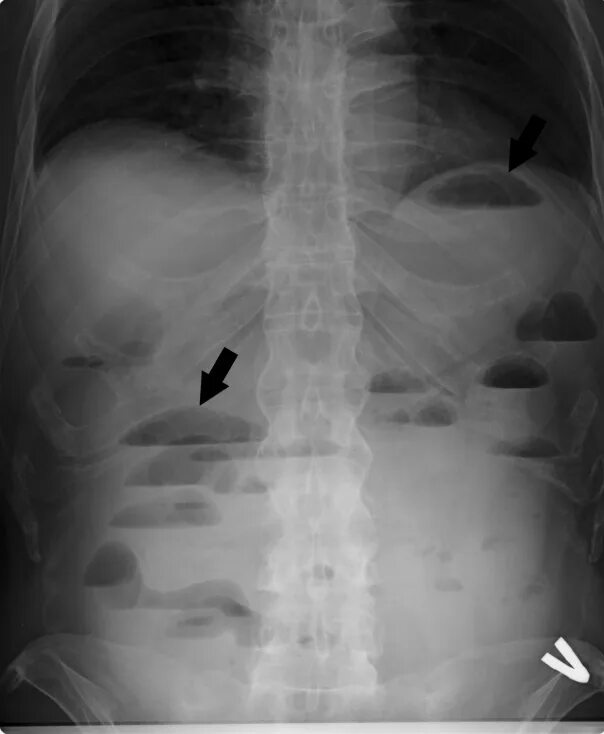

Симптом чаши